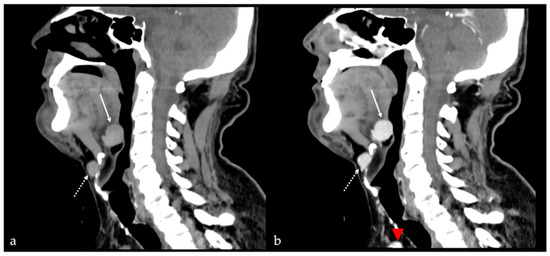

7.1. Thyroglossal Duct Cyst

| Arteriovenous malformation [6,12] | MRA: arterial feeding vessel, nidus, and venous drainage vessels MRI: flow voids | Other vascular malformations |